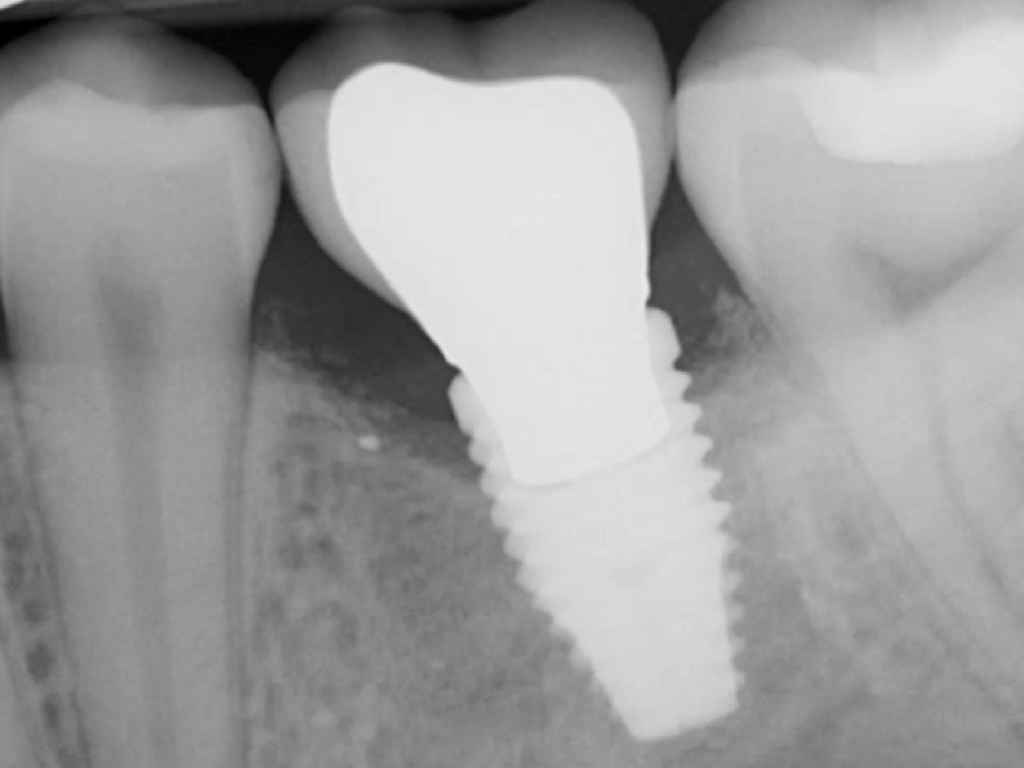

Similar to natural teeth, measurements of PPD and BoP before and after treatment are clinical parameters often used to determine the health of dental implants (Figure 4 and Figure 5). However, due to the difference between periodontal and peri-implant anatomy, concerns have been raised about the use of probes in peri-implant tissues around dental implants. These include the risk of peri-implant tissue damage,17,18 risk of damage to the implant surface by the metallic probe,19-21 risk of bacteria inoculation,22-27 and risk of galvanic corrosion resulting from contact between two dissimilar metals.21,28-30 These risks are discussed in the following sections.

Probing the sulcular depth around a dental implant is an important clinical exercise to assess implant health and stability. Longitudinal measurement of probing depth helps monitor the integrity of the peri-implant tissues. An increase in the probing depth usually indicates loss of alveolar bone support. Increasing probing depth over time in the presence of BoP and gingival exudate are criteria to diagnose peri-implant disease.33 Increased probing depth accompanied by BoP without concomitant bone loss has been defined as peri-implant mucositis.34 When these signs are present with radiographic (or sounding) evidence of bone loss, the disease has been defined as peri-implantitis.34

Due to the various aforementioned factors that can affect probing depth around an implant, a probing depth of 4 mm to 5 mm around an implant may not be as critical a diagnostic parameter as it would be around natural teeth (Figure 9 and Figure 10). However, probing depth accompanied by BoP becomes a significant concern around an implant. Therefore, while incidental measurement may not be indicative of the health status of the peri-implant tissue, probing at various time intervals enables assessment of health status and disease progression.

Fig 4. Increased probing depth around an implant with BoP indicates presence of peri-implant disease and the need for taking a radiograph.

Figure 4

Fig 5. Bone loss shown on radiograph confirms the presence of peri-implantitis and peri-mucositis.

Figure 5